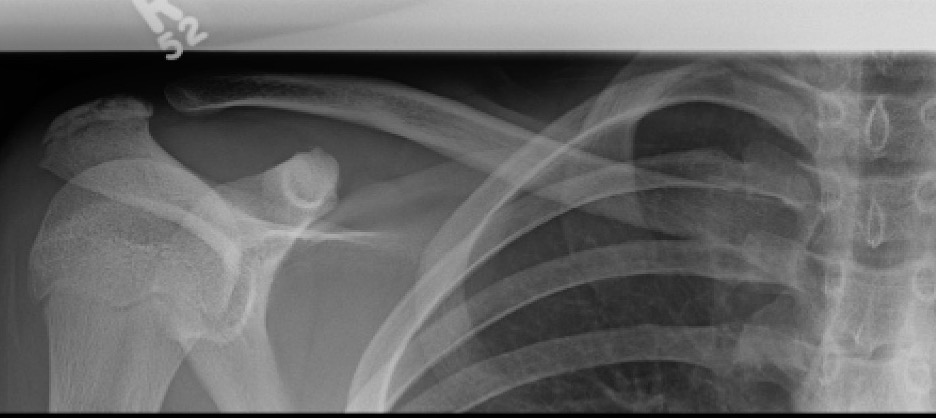

Xray

Can be missed on a xray

CT scan

Left posterior SCJ dislocation with pre- and post angiogram

Left posterior SCJ dislocation with pre- and post angiogram

Severe left posterior SCJ dislocation with subclavian vein compression